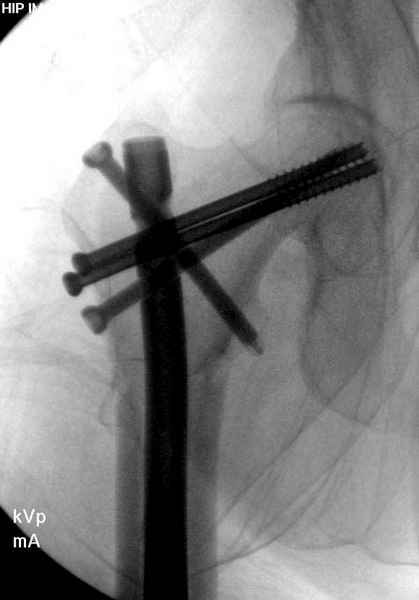

Правильно, ситуация изменилась, как говорят у нас теперь "different animal", надо решать проблему подвертельного перелома. При наличии различных вариантов фиксаторов, включая Страйкер Гамма 3, мы выбрали DePuy Antegrade Trachanteric Nail из-за многовариантности проксимальной фиксации и двойного изгиба. Вводится через вертел под 8 градусным углом, и есть достаточный передний диафизарный изгиб, предупреждающий пенетрацию дистального переднего кортекса.